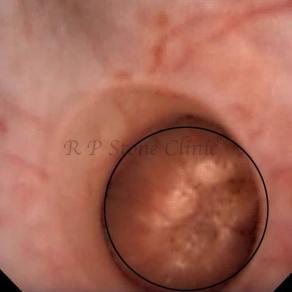

The Below Images Show Small Stones attached to the Renal Papillae.

These images are taken as snap shots from the video recording of RIRS Surgery done at our hospital. These are Randall’s Plaques seen with Digital FLEX XC & Digital FLEX XC S. The cream or whitish patches are seen on the tips of RENAL PAPILLAE as seen in images below.